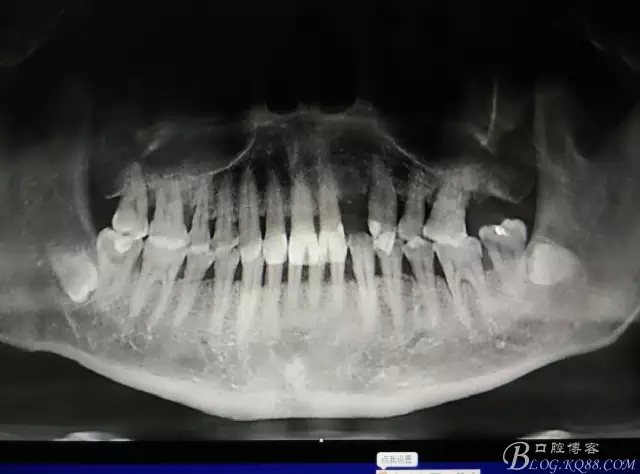

患者、楊xx、男、49歲。主訴:左側(cè)前牙拔除半年,活動(dòng)義齒修復(fù)四個(gè)月,要求種植修復(fù)。??茩z查:21缺失,牙槽粘膜厚度正常。CBCT檢查:高度16mm,寬度7mm.術(shù)前簽知情同意書。

圖1.術(shù)前的CBCT檢查:22缺失。